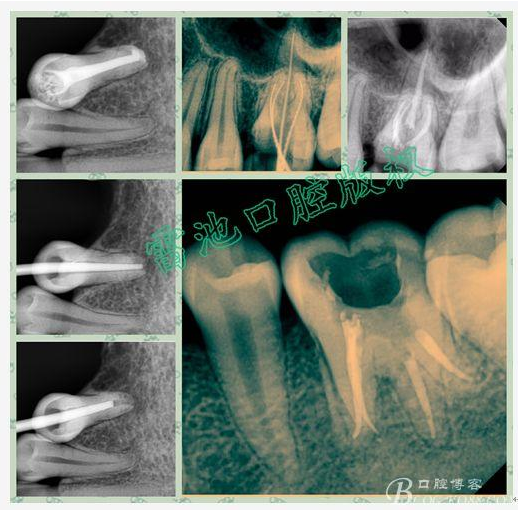

E 、X線影像學(xué)的檢查研判能力: 這點(diǎn)不需要強(qiáng)調(diào)太多,對(duì)于普通的非CBCT的二維影像對(duì)醫(yī)生讀片能力有一定的要求,有個(gè)逐步提高的過(guò)程,非一蹴而就,需要學(xué)會(huì)把二維的X線影像與三維的解剖結(jié)構(gòu)進(jìn)行良好的對(duì)應(yīng)結(jié)合,對(duì)于某些鈣化的髓室底,應(yīng)通過(guò)想象把根管口的分布、根管的走向以及各種變化通過(guò)想象投射到對(duì)應(yīng)的髓室底上;

G:找尋MB2的問(wèn)題:

1、查閱各種文獻(xiàn),MB2的發(fā)生率在52-96%之間,治療時(shí)遺漏是上頜磨牙根管治療失敗的主因,2、一般位于MB1根管口與腭根管口方向的0.5-5mm范圍內(nèi),而大多數(shù)都位于MB舌側(cè)的1-3mm處,其中2mm以內(nèi)占85.7%,3、MB1-P根管口連線與MB1-MB2根管口的連線夾角大部分(74.3%)在30度以內(nèi);4、MB2的尋找大部分需要去除相應(yīng)部位的牙本質(zhì);5、當(dāng)找到的MB根管口呈“長(zhǎng)線型”且有深色凹線向舌側(cè),或者找到的MB根管口明顯偏頰多提示有MB2的可能;6、DOM(牙科手術(shù)顯微鏡)的使用有助于找尋MB2;